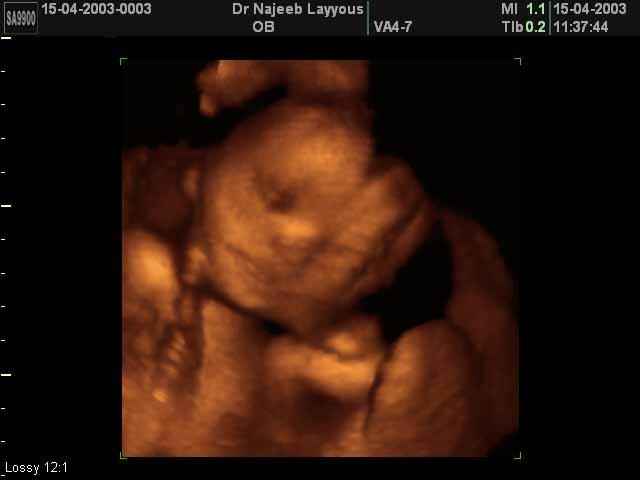

- Fetal Behavior Ultrasound Photos

3D Second Trimester Ultrasound Scan Photos-second part of pregnancy | Dr N Layyous